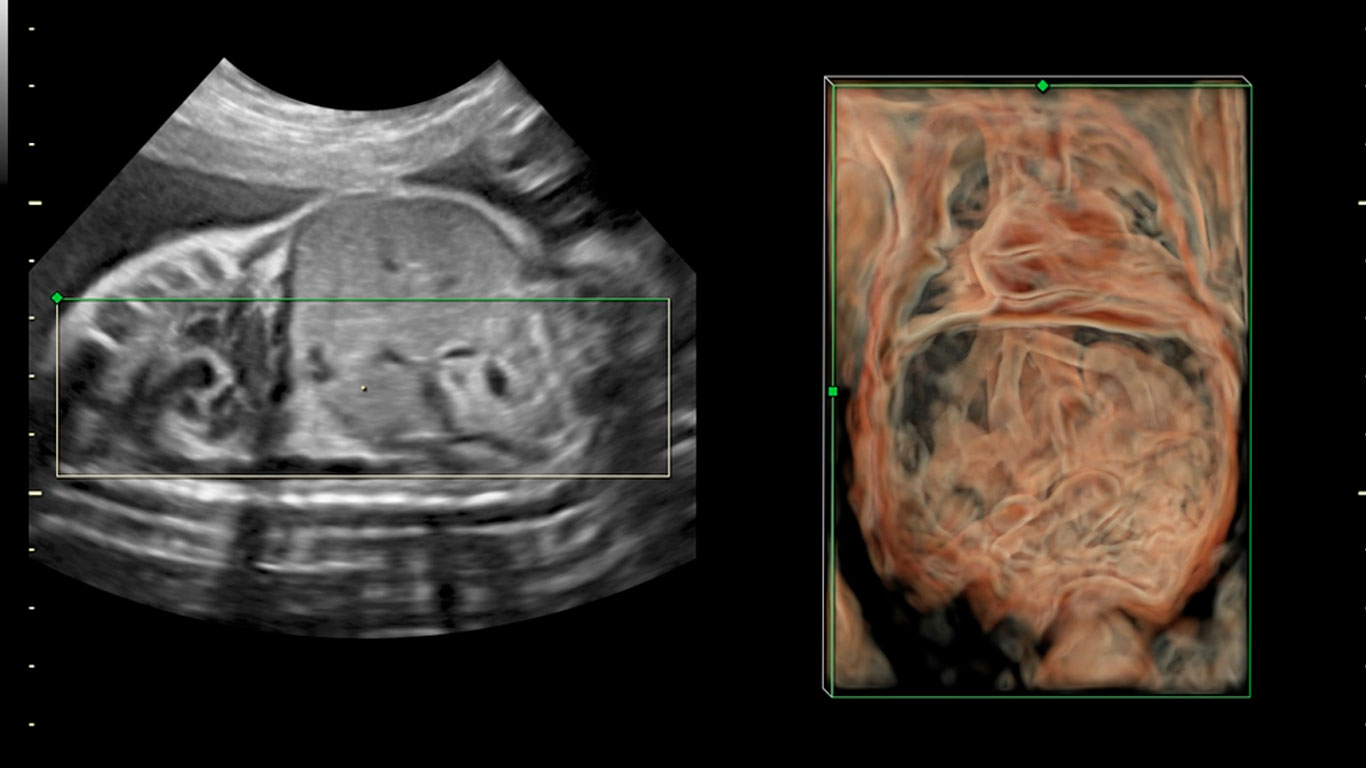

“Estos equipos tienen múltiples recursos que realmente me permiten, no solo cumplir con las expectativas diagnósticas de los colegas, sino siempre ir un poco más allá”.

Dr. Juan Fajardo

Radiólogo

«Los avances que se han conseguido en los Voluson en los últimos años son muy elevados y eso permite unos diagnósticos precisos y un manejo más amigable para el profesional».

Dr. Eduard Gratacós

Ginecobstetra